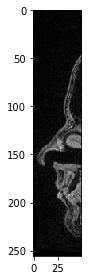

Para visualizar imágenes 3D usando imshow de scikit-image, necesitamos seleccionar un corte para visualizar. Por ejemplo, un corte en Z:

slice_image = image[100]

imshow(slice_image)

../_images/b9ec53895c9942461dd35e1b88b95a9557441ceb09c074bd865d8bb6ddfdb74b.png